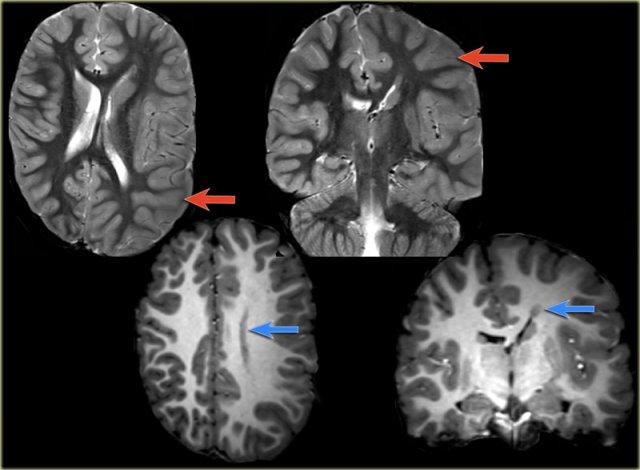

Hình ảnh T2W và FLAIR mặt phẳng coronal cho thấy xơ cứng thùy thái dương trong bên phải.

Lưu ý tình trạng mất thể tích, biểu hiện của teo não, gây giãn thứ phát sừng thái dương của não thất bên.

Tín hiệu cao trong hải mã phản ánh tình trạng gliosis.

Hình ảnh cho thấy xơ cứng thùy thái dương trong với hải mã tăng tín hiệu và teo nhỏ (mũi tên đỏ), kèm theo giãn thứ phát sừng thái dương trái của não thất bên trái.

Cũng cần lưu ý tình trạng tăng tín hiệu dưới vỏ não kết hợp ở thùy thái dương trái, gợi ý loạn sản vỏ não khu trú.

Xơ cứng thùy thái dương trong bên trái. Gliosis kín đáo của hải mã trái (mũi tên xanh dương) và teo não (mũi tên vàng).

Bệnh nhân 35 tuổi với động kinh thùy thái dương kháng trị.

MRI cho thấy tăng tín hiệu kín đáo của hải mã trái trên chuỗi xung FLAIR axial (mũi tên xanh dương) và teo hải mã trái trên hình ảnh coronal (mũi tên vàng).

Bệnh nhân được điều trị thành công bằng phẫu thuật cắt hạnh nhân – hải mã bên trái.